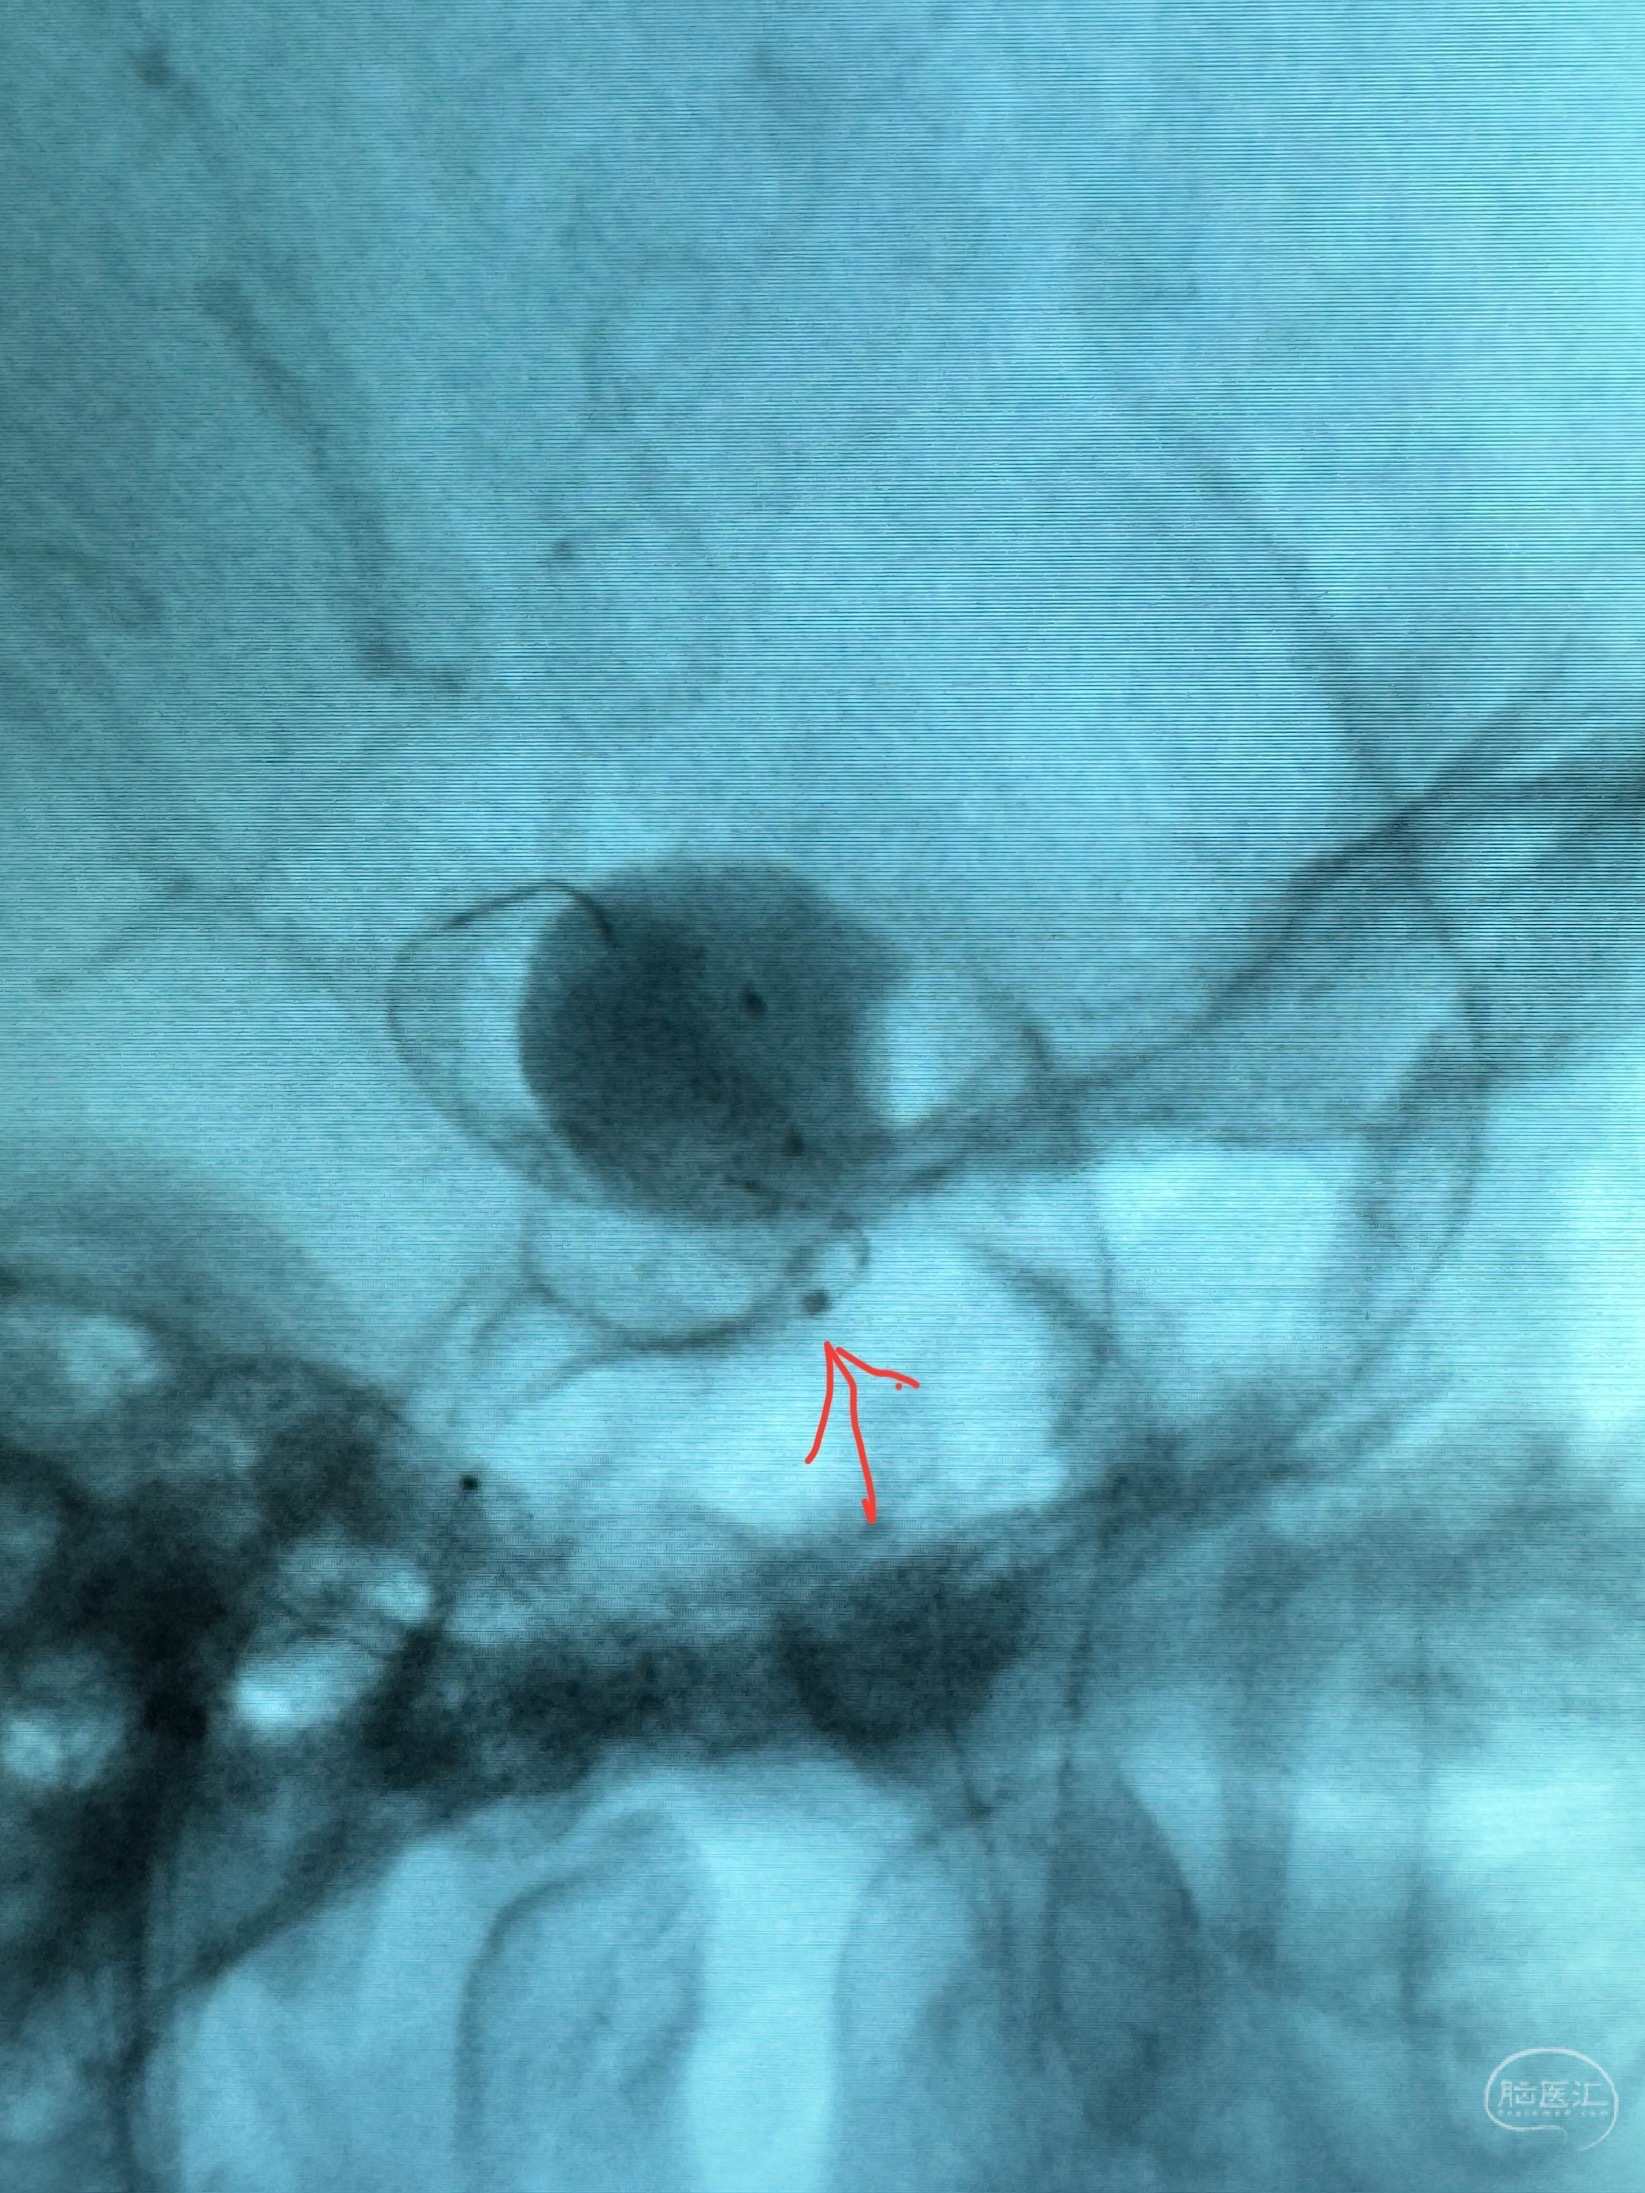

手推冒烟显示支架位置及展开情况,箭头为支架导管的位置

尝试回收支架失败,只能考虑释放支架了

逐帧图像展示歪着脖子释放支架,旁边吩咐助手手机摄影、拍照留像(透视机不能留影像)